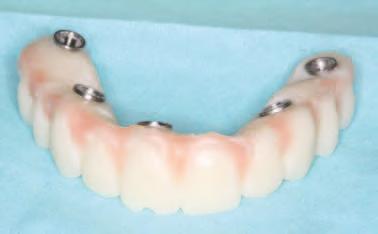

FREZAREA ȘI FINISAREA RESTAURĂRILOR

După f nal zarea procesulu de proectare, restaurăr le au fost frezate d ntr-o z rcon e mult cromat că cu transluc d tate r d cată într-o mașnă de frezare cu c nc axe. Procesul de frezare poate dura până la 7 ore pentru o arcadă. Z rcon a modernă este d spon b lă într-o translucd tate r d cată pentru o apar ț e estet că ma naturală, ar coloraț le mult cromat ce sunt ntegrate. Acest lucru perm te tehn c en lor să fabr ce un des gn monol t c cu un grad ent natural de la o zonă cerv cală ma cromat că la o zonă nc zală ma transluc dă.

În z ua următoare, s-a ut l zat ceram ca roz pentru a restab l estet ca max larulu , ar colorarea ș glazurarea au fost folos te pentru a f n sa estet ca generală atât pentru max lar, cât ș pentru mand bulă. Folos rea ceram c roz sau a așa-num telor ceram c l ch de este încă necesară pentru a restaura estet ca roz, întrucât performanța doar a p gmentăr ș glazurăr pentru mater alul actual nu maschează adecvat z rcon a pentru a ofer o estet că g ng vală naturală.

În cab net, restaurăr le prov zor au fost deșurubate ș îndepărtate d n cav tatea orală pentru ca restaurăr le f nale să poată f l vrate ș strânse cu un cuplu de 15 Ncm, conform recomandăr producătorulu (f g. 15,16). Ajustăr le ocluzale f nale au fost m n me ș efectuate ntraoral pr ntr-o ultmă lustru re a zonelor ajustate.

15. Vedere extraorală a restaurărilor finale livrate.

16. Vedere intraorală a restaurărilor finale mandibulare livrate.